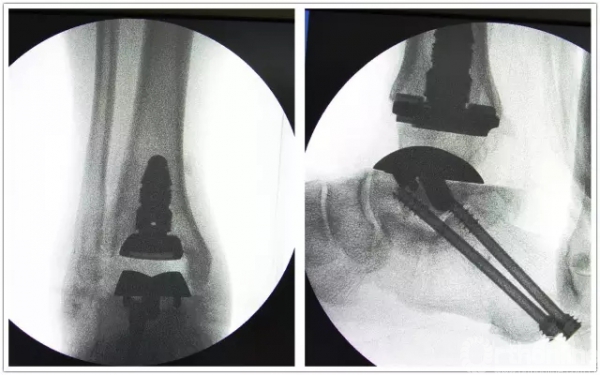

手术中首先沿原手术切口进入,保护神经血管肌腱组织,清理踝关节假体周围骨赘,取出原关节假体,将患足置于专门的定制支架中,在透视下反复调整足踝及导针位置,力求最高精确度。在导板的定位下进行胫骨远端和距骨截骨,试样假体大小,置入合适匹配的踝关节假体及垫片完成全踝关节假体的置换,然后再行距下关节融合术。历经4小时,手术过程非常顺利,术后患者恢复良好,手术取得圆满成功。